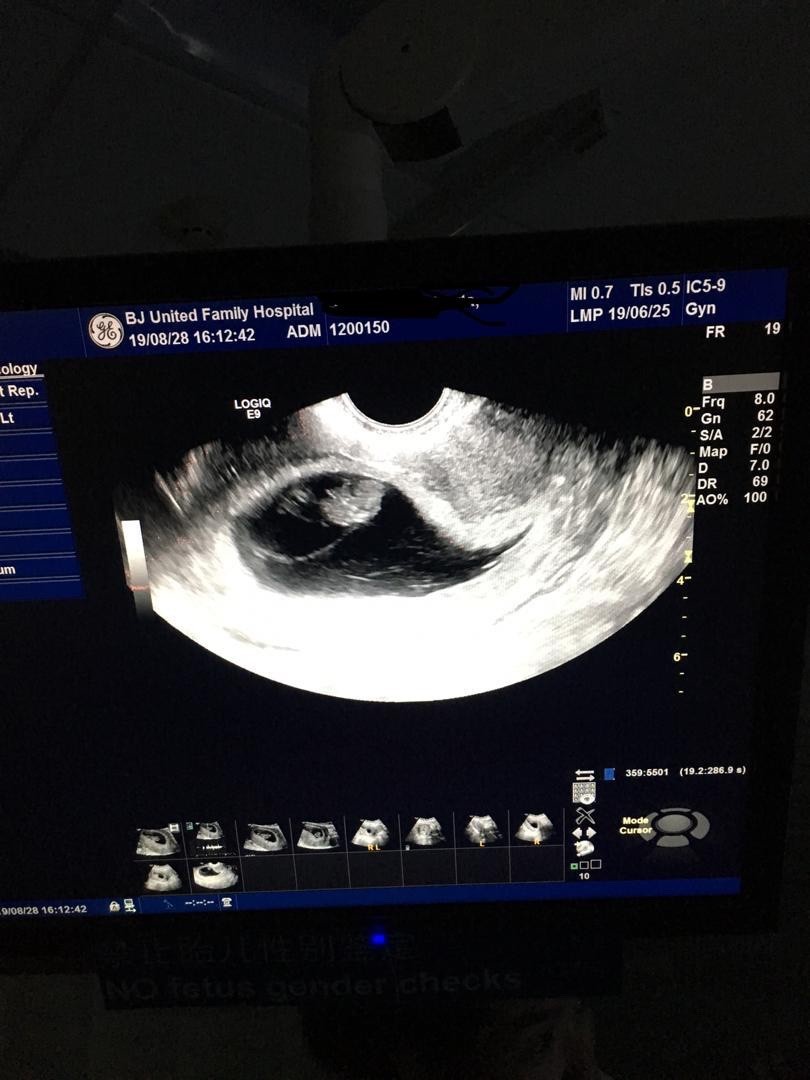

Zdjecie juz nieaktualne, bo z zeszlej srody;) , ale sie pochwale. Wtedy wg OM 9t1d wg usg 8t6d, dzidzia 2,20 cm fhr 170. Przy poprzedniej wizycie 6t3 d wg usg dzidzia miala 0,6 cm I fhr 108.Zobacz załącznik 1018606